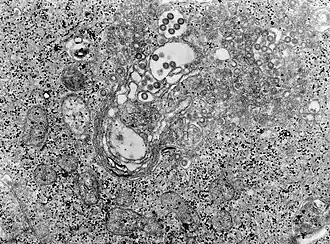

| Původce | TEM mikrosnímek tkáně infikované virem horečky riftového údolí |